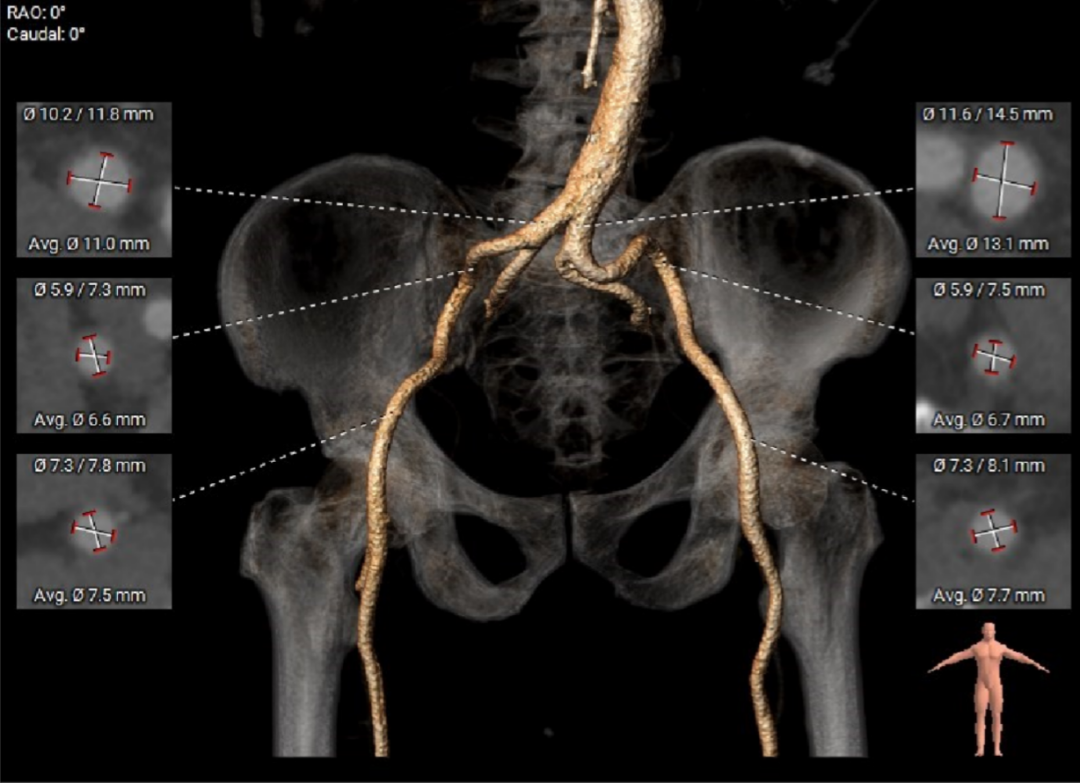

外周血管及主动脉弓解剖

入路血管存在较大迂曲,双侧血管内径良好,主动脉弓部夹角及弓距尚可。